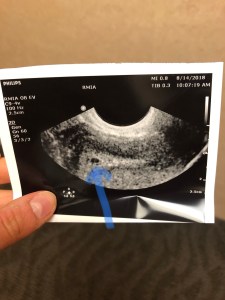

Our next appointment was a follow up blood draw on Monday morning, August 6th. Once a positive pregnancy test is confirmed in the clinic, every IVF patient must go in for a confirmatory blood draw 48-72 hours later to ensure that the woman’s HCG (pregnancy hormone) levels are rising appropriately. According to our clinic, the HCG level should double every 48 hours. Our initial result on Friday was 52, and on Monday, it had risen to 107.3. Although the level technically doubled, our doctor requested one additional blood draw to be done on Wednesday, just to be sure everything was progressing. I should note that while going through the journey of infertility, I’ve constantly felt like something is wrong with me. Like I’m not enough. I’ve felt as if I’m not worthy of having a child, and perhaps I am being punished for something. So when our HCG levels weren’t rising at the rate our clinic had hoped, I yet again felt as if I was climbing a mountain too high for me to conquer. But on Wednesday afternoon, our lab result was 247.9, and on the following Monday, 1,198. Our pregnancy was official! We were told our due date would be April 11th, 2019, and our first ultrasound would be at 5 weeks, 5 days. That five-week ultrasound showed a beautiful gestational sac, and while we were told it was a bit too early to see the baby or the heartbeat, we could not wait for our next ultrasound in just over a week.

On Tuesday, August 21st, Dave and I got to the clinic early, hopeful and eager to see our little baby growing. We were brought back to the ultrasound room and everything went as it normally did. But when our tech placed the probe to view my uterus, the empty sac was all to be seen. And her face told the rest of the story. I gripped Dave’s hand tightly, waiting to hear confirmation of what I already knew to be true. We had lost our pregnancy. She stated how she was so sorry, but there was no fetal development. It appeared that our pregnancy had stopped progressing, and she stepped out to give us the time we needed. I laid on the table with my hands over my eyes, sobbing uncontrollably. For the first time, Dave was not jumping up to immediately comfort me with positivity. He was by my side, with his own hands over his eyes, also crying. Eventually he helped guide me off the table and held my body as I wept. And he continued to do the same. We met with the clinic staff member to discuss what our next steps would be – we could either wait to miscarry naturally, or I could have a surgical procedure called a Dilation and Curettage (better known as a D&C) to remove the contents of the pregnancy. The surgical option would allow us to complete genetic testing and help determine why this loss took place. We chose that option, and fortunately, my OB was able to get me in the following day. Those next 24 hours were honestly a blur to me. I went into work, because I didn’t know what else to do. But I’m fairly certain that while I was present physically, I was emotionally vacant and completely disconnected. The D&C was a relatively simple procedure from a recovery standpoint, but it took weeks for me to feel even remotely close to myself again. I decided to share with my coworkers, and several other people close to me, so I did not have to slap on a happy face when all I felt was heartbreak. I felt a great degree of healing once I became open with the individuals who I spend a large portion of my life with. The flood of messages, prayers, and most surprisingly, people who shared their own similar journey, made me feel not quite so alone. Our genetic test revealed that our baby had a chromosomal abnormality called Trisomy 16. As difficult as it was to hear this, it provided a reason for the loss, and helped me to know that I didn’t do anything wrong.